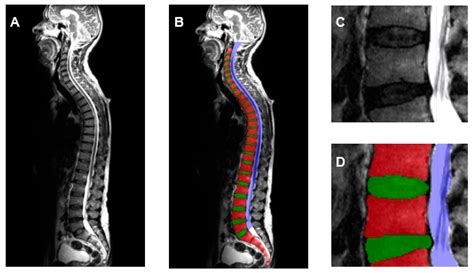

Application of a Deep Learning Approach to Analyze Large-Scale MRI Data ...

mdpi.com